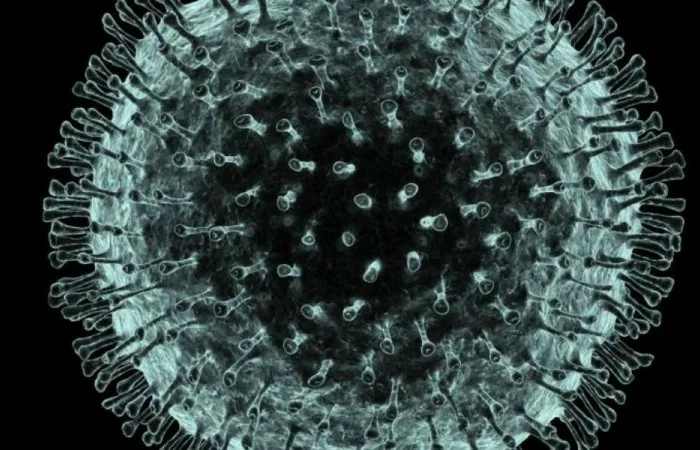

চট্টগ্রামে করোনা ভাইরাসে ৬ বছরের শিশুর মৃত্যু

চট্টগ্রাম নগরীতে করোনাভাইরাসে আক্রান্ত ছয় বছর বয়সী এক শিশুর মৃত্যু হয়েছে।

করোনা শনাক্ত হওয়ার পর ছয় বছর বয়সী ওই শিশুকে রোববার রাতে চট্টগ্রাম জেনারেল হাসপাতালের করোনা ইউনিটে নেওয়া হয়ে। সেখানে রাত আড়াইটার দিকে শিশু আশরাফুলের মৃত্যু হয়।চট্টগ্রামে করোনায় এটি দ্বিতীয় মৃত্যু ।

শিশুটি পটিয়া উপজেলার হাইদগাঁও ইউনিয়নের ১নং ওয়ার্ড ওসমান পাড়ার খলিলুর রহমানের পুত্র। স্বাস্থ্য অধিদপ্তরের চট্টগ্রাম বিভাগীয় পরিচালক ডা. হাসান শাহরিয়ার কবির তথ্যের সত্যতা নিশ্চিত করেছেন। তিনি দিগন্ত নিউজ বিডি কে বলেন, ‘গতকাল চট্টগ্রামে শনাক্ত করোনা আক্রান্ত ছয় জনের মধ্যে এই শিশু একজন। গত তিন দিন ধরে শিশুটি জ্বর ও ডায়রিয়ায় ভুগছিল।